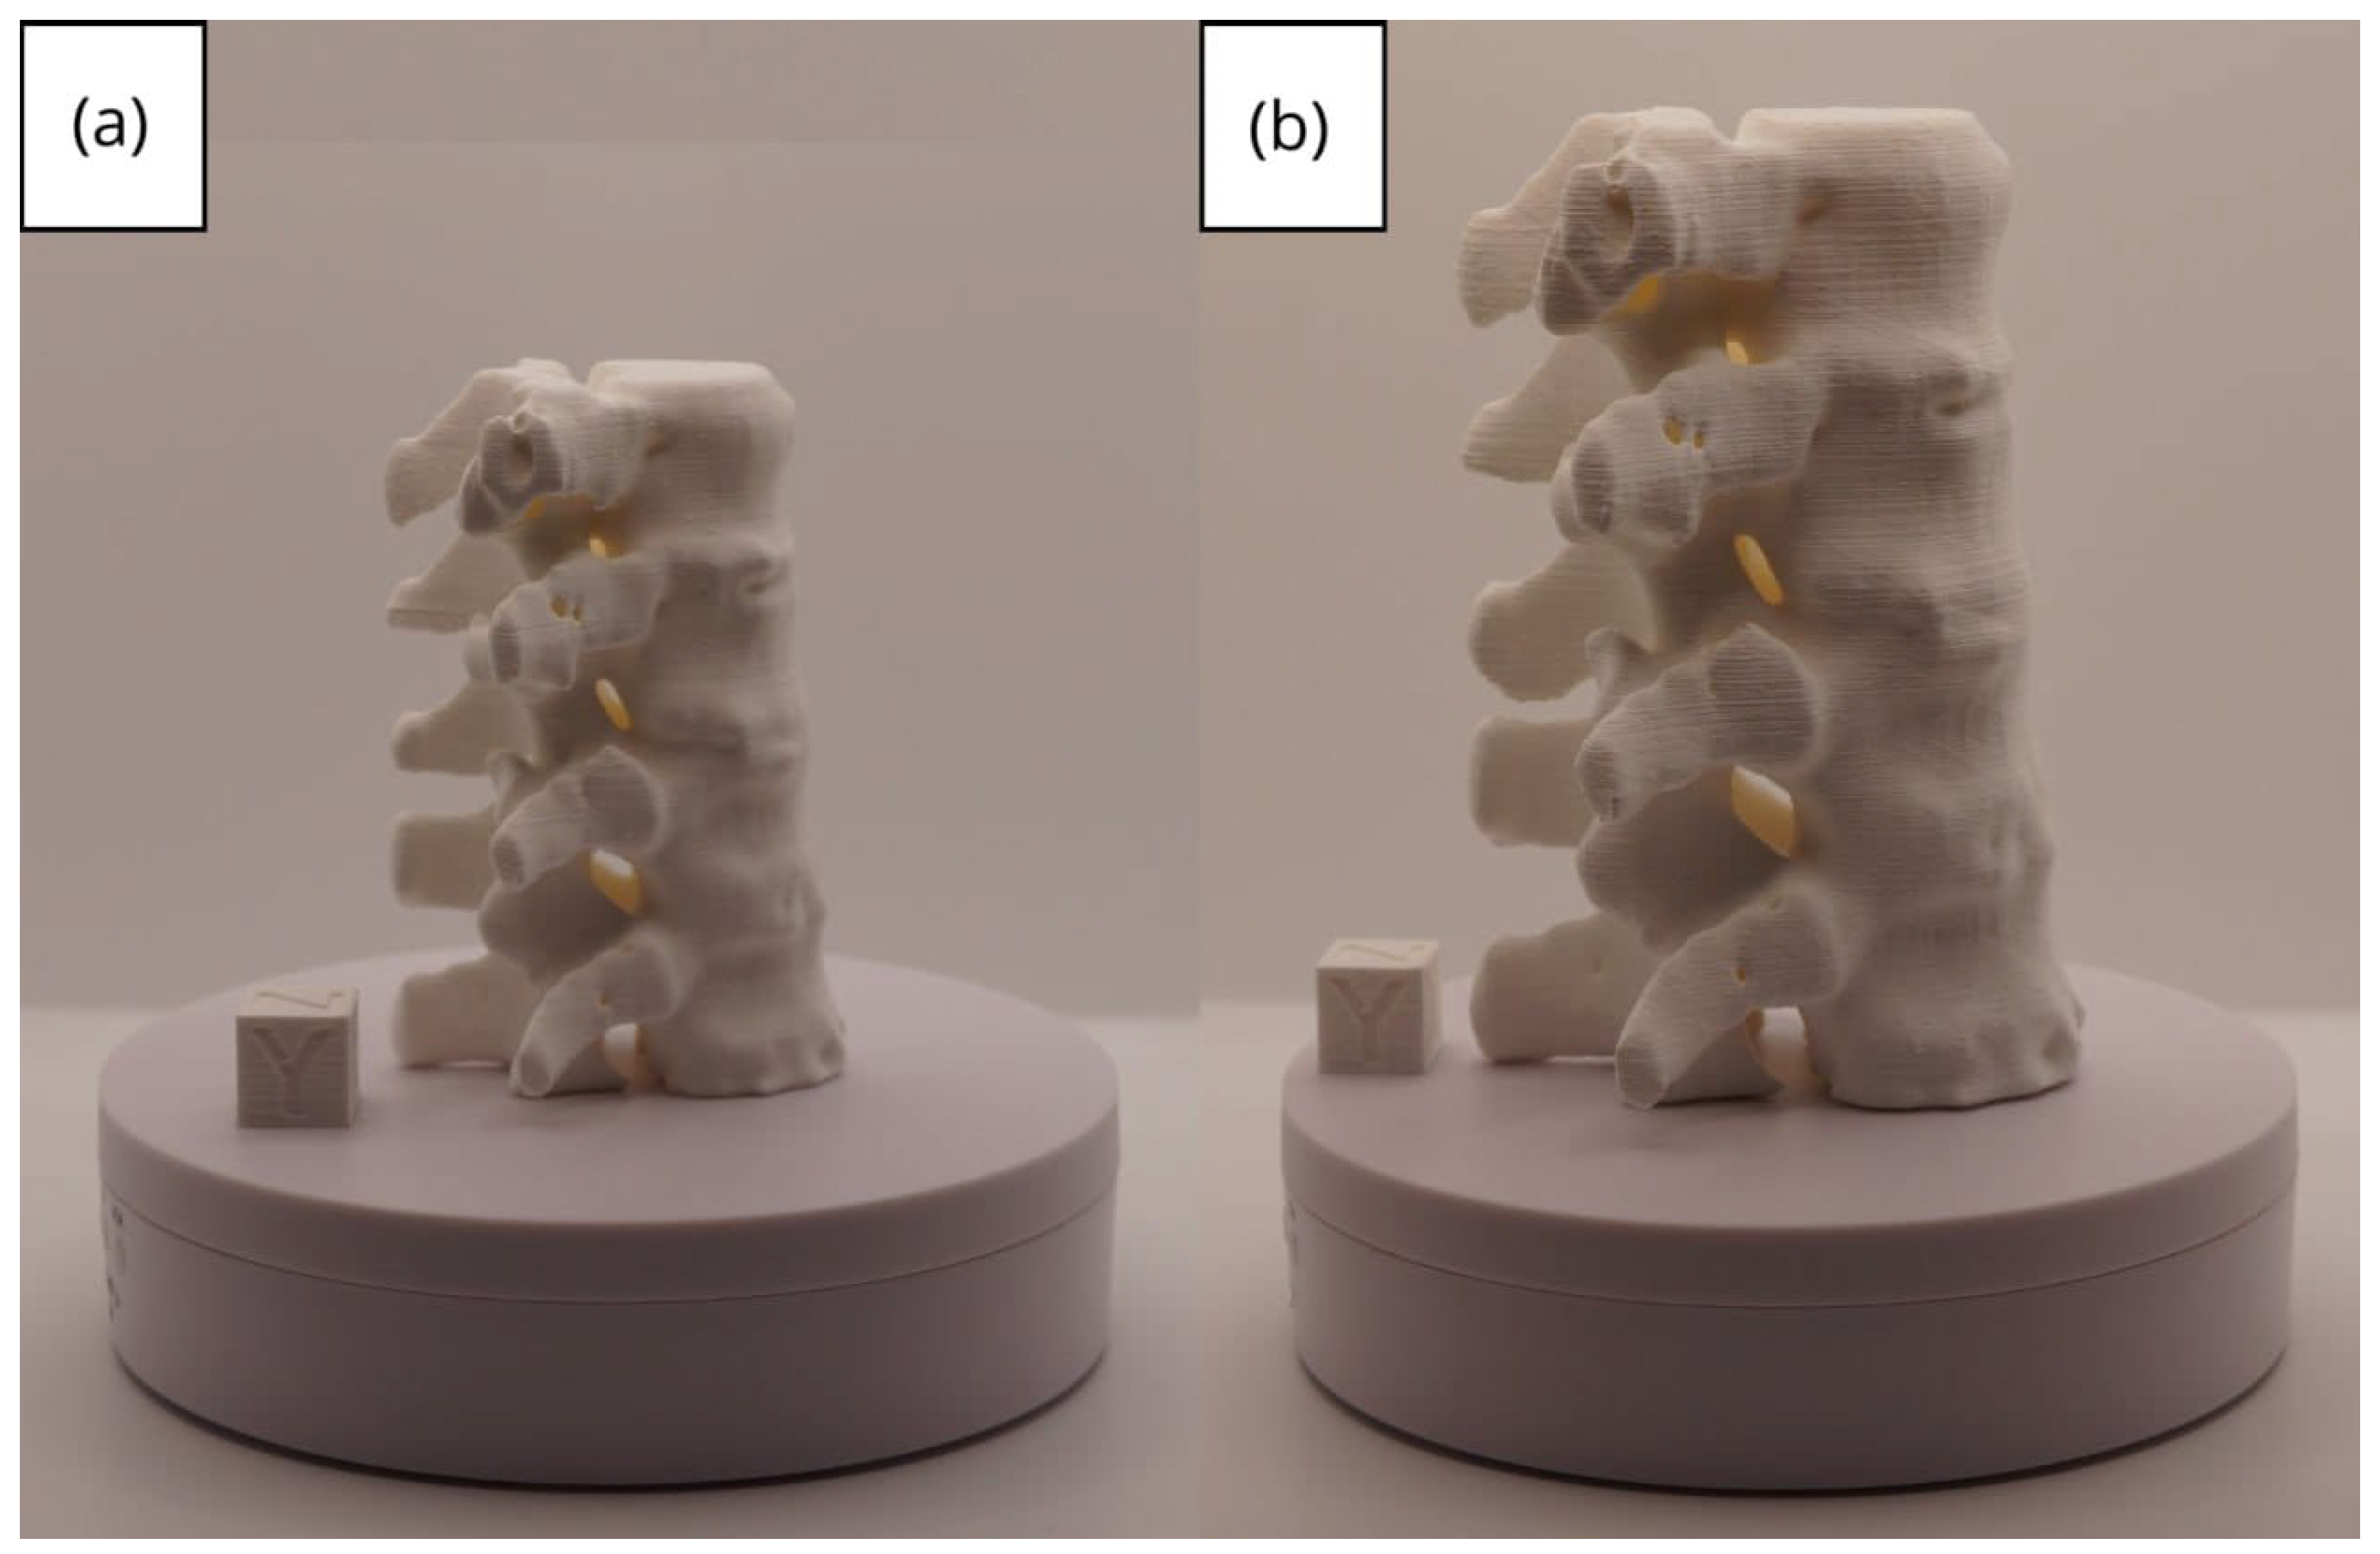

3.2. Human Lower Jaw

3.2.1. DICOM-to-STL Files

3.2.2. STL-to-GCODE Files

3.2.3. Final Printing

| Jawbone | [100, 250] | Gaussian | 0.6 | 0.20 | 40 |

| Lower jaw models | m; m | Artillery Sidewinder X2 |

| m; m | Creality Ender 3 | |